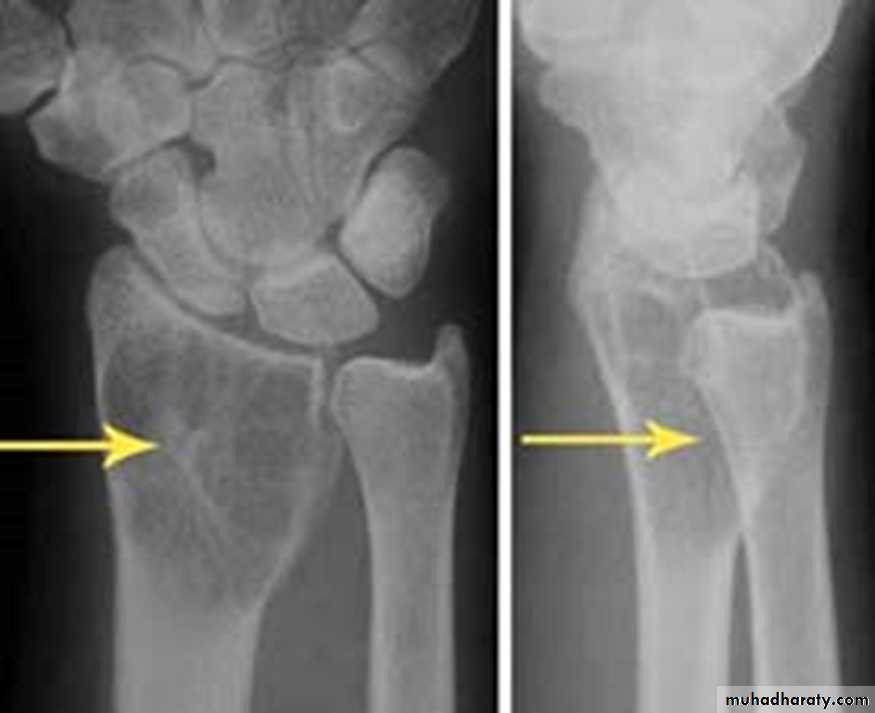

Giant cell tumor:Slowly growing , locally invasive, rarely metastasize.

Age: after closure of epiphysis (20-40 years).

Site: around knee & wrist joints.

Findings:

lytic, expansile lesion,

Sub articular in location,

Not clearly defined margin,

thinning of the cortex (sometimes with destruction of cortex)